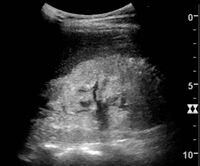

The kidney is divided into parenchyma and renal sinus. The renal sinus is hyperechoic and is composed of calyces, the renal pelvis, fat and the major intrarenal vessels. In the normal kidney, the urinary collecting system in the renal sinus is not visible, but it creates a heteroechoic appearance with the interposed fat and vessels. The parenchyma is more hypoechoic and homogenous and is divided into the outermost cortex and the innermost and slightly less echogenic medullary pyramids. Between the pyramids are the cortical infoldings, called columns of Bertin (Figure 1). In the pediatric patient, it is easier to differentiate the hypoechoic medullar pyramids from the more echogenic peripheral zone of the cortex in the parenchyma rim, as well as the columns of Bertin (Figure 2).[1]

Figure 2. Normal pediatric kidney. * Column of Bertin; ** pyramid; *** cortex; **** sinus.[1]